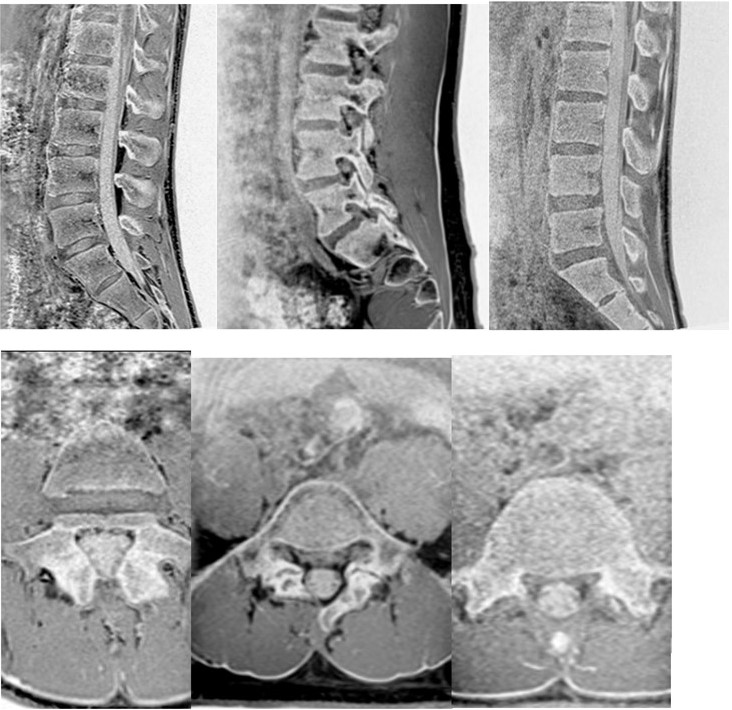

➀初期ではレントゲンで分離像を認められないのが一般的です。CTではよく見ると分離部がわかります。MRIでは脂肪抑制画像で椎弓の骨髄浮腫が白く確認でき、初期分離症の早期診断が可能です。

②進行期ではレントゲンやCTで進行度合い(病期)や分離部の骨癒合の経過を判断していき、MRIの脂肪抑制画像で骨髄浮腫の状態を確認していきます。終末期ではレントゲンで分離像が認められます。CTは分離の程度を確認し、MRIの脂肪抑制画像では骨髄浮腫が完全に消失していきます。

腰椎分離症ではMRIとCT両方の画像が必要になります。クリニックで両方の機器を備えている施設はあまりなく、CTを繰り返し受けることにより放射線の被ばくも伴います。MRI検査は強力な磁気を使用した検査であり放射線の被ばくがないため、安心・安全に検査を受けていただく事が可能です。

当院ではレントゲンとMRIで経過観察できないものかと考えていました。最近のMRI撮像技術の進歩によりCTに似た骨画像(Boneimage)が撮像できるようになり、積極的にこの撮像をしております。骨画像を活用しそれぞれと組み合わせていくことで診断向上に努めております。(必要に応じてCTも撮影していただく事もあります)